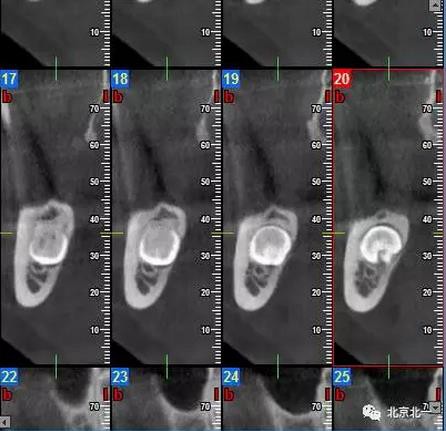

圖三:截面圖顯示神經(jīng)管位置。